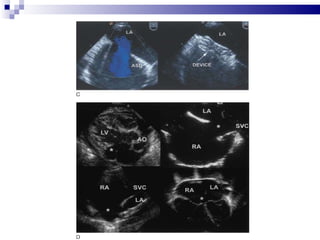

LA RA RUPV RV

LA LA RA RA Fig 9

LA LA RARA Fig 9